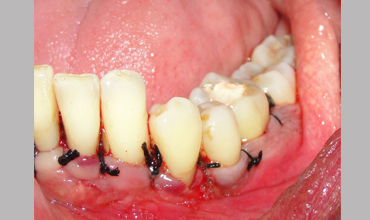

NON SURGICAL MANAGEMENT OF ENDODONTIC LESION AND SURGICAL MANAGEMENT OF PERIODONTIC LESION